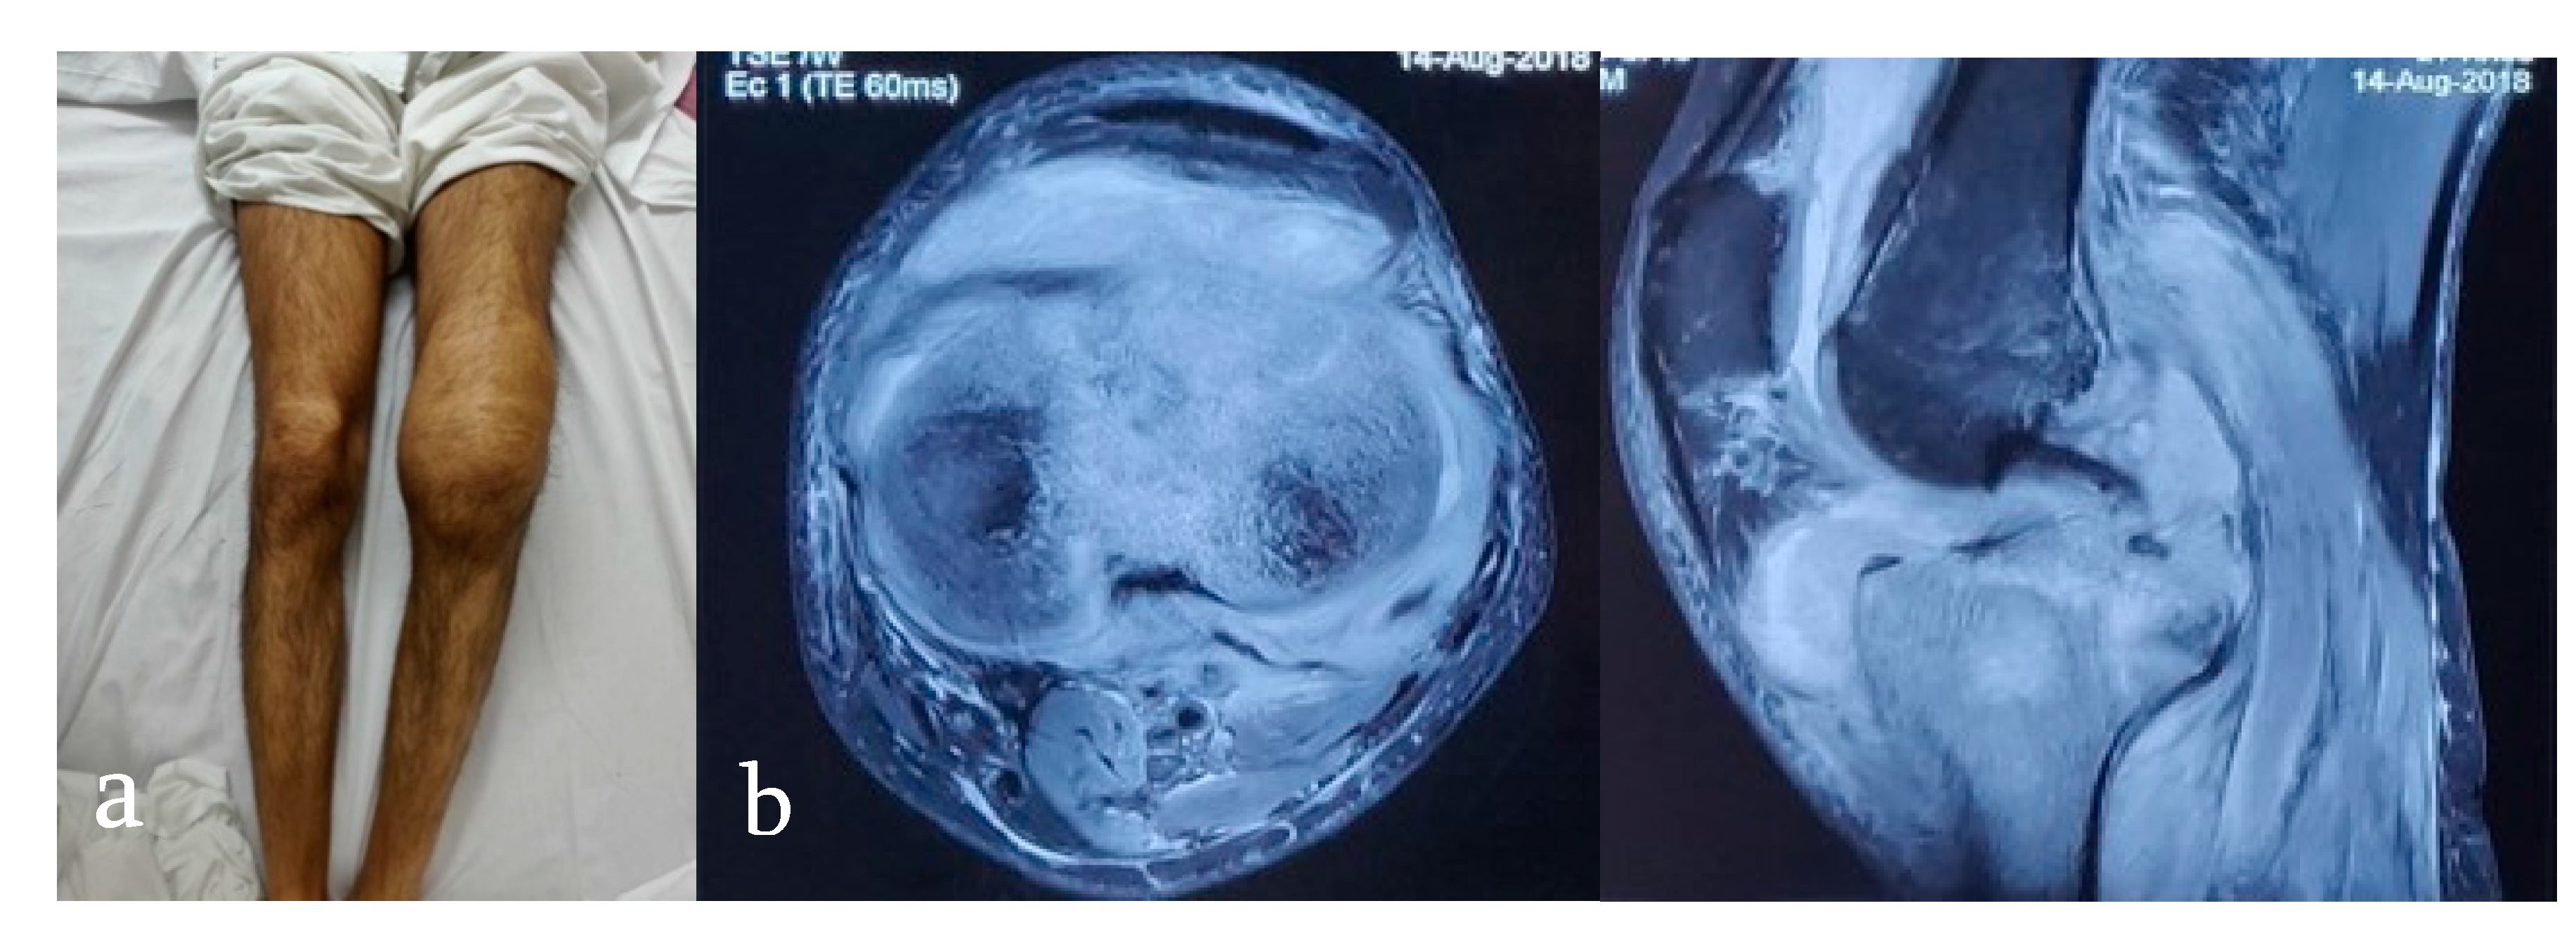

- Wagh, Y.; Reddy, R.; Gundavda, M.; Agarwal, M.; Agashe, V.M.; Bajwa, S. Tuberculosis (T.B.) masquerading as tumor. An 8-year study on 25 cases of long bone tuberculosis presenting as tumors. SICOT-J 2020, 6, 14. [Google Scholar] [CrossRef] [PubMed]